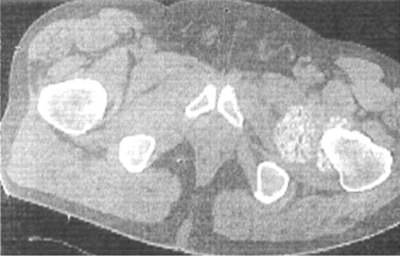

CT表现:28例接受平片扫描的患者能清楚显示软骨瘤结节。结果表明,结节位于关节囊16例,滑膜囊5例,关节囊和滑膜囊4例,腱鞘3例。CT扫描显示21例伴有不同程度的边缘骨质增生和关节积液,12例伴有关节滑膜增厚。左侧髋关节病变有2例分叶状肿块,伴有髋臼骨吸收破坏和钙化软骨瘤结节(图2)。

图2